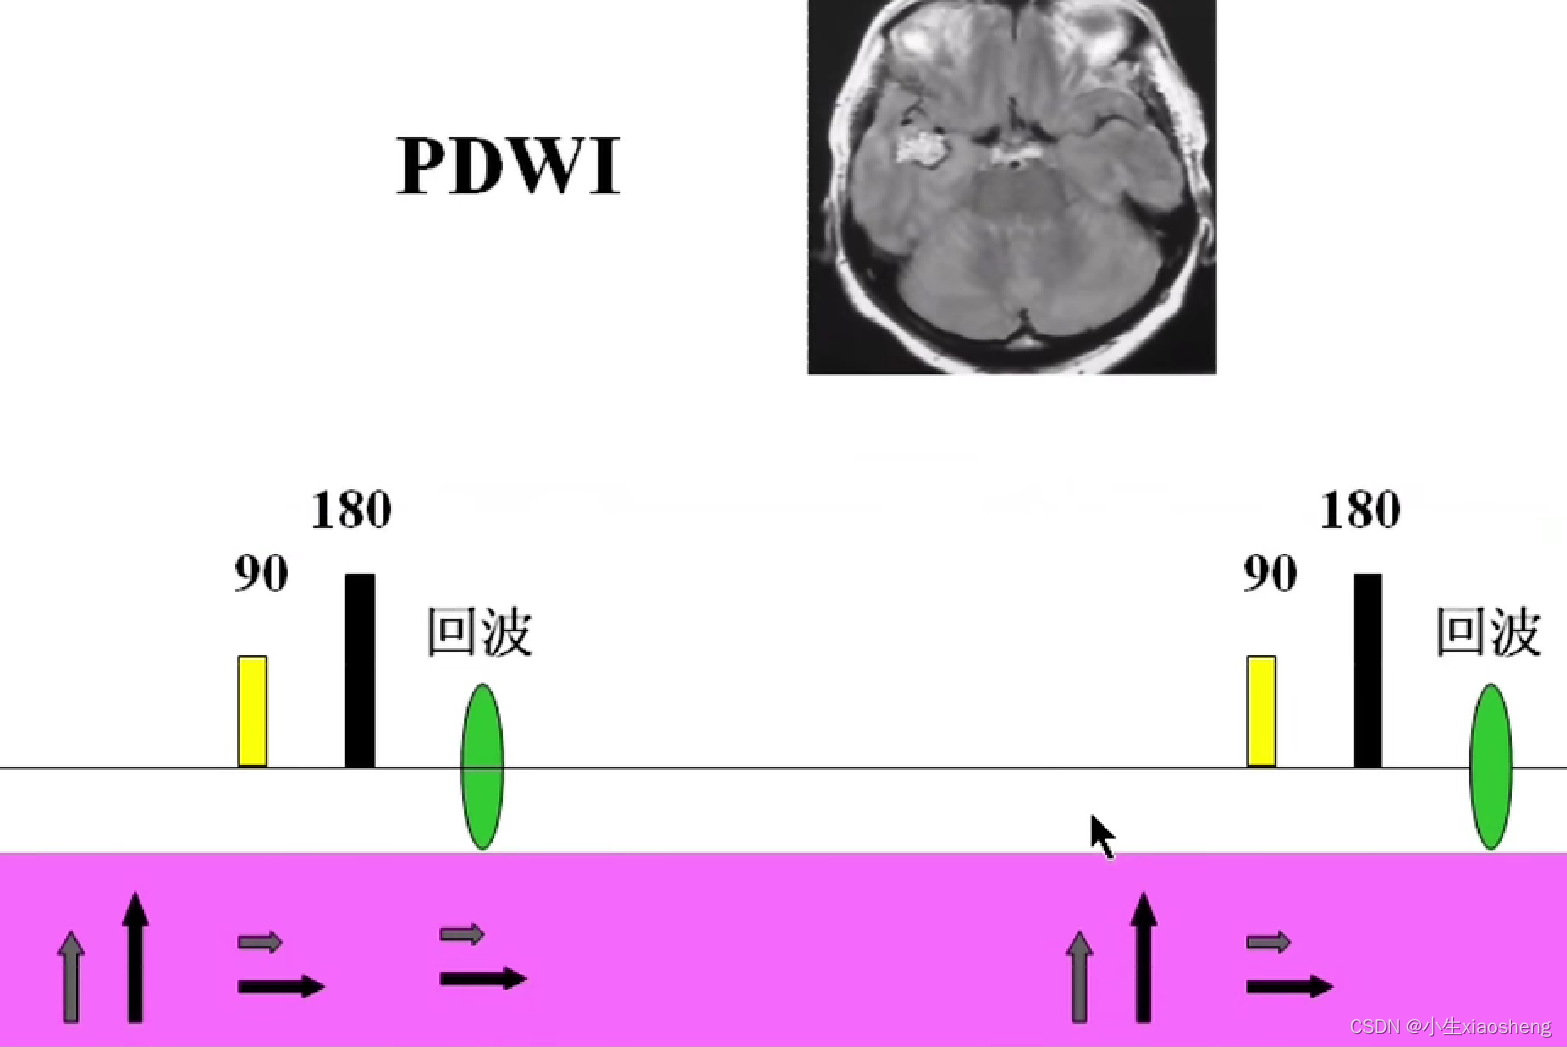

90度和180度共同来组成一条K空间线。

180度的意思就是改变终点的方向,恢复慢的离终点近,恢复快的离终点远,到时候一起到。这样就比原来的弛豫下降的时间要长了。

因为这里有很多的180度,所以一次能填充很多K空间线。两个90度之间的时间还是叫做TR,180度的个数叫做ETL,90度到中间个数的180度叫做有效TE,两个180度之间的叫做ES。